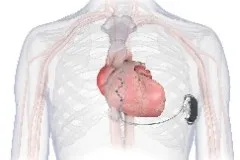

血管外植入式心律转发除颤器

植入式心律转复除颤器(ICD)是预防心脏性猝死最有效的治疗措施。目前在国内临床使用的ICD系统分为两种类型:经静脉ICD系统和皮下ICD系统。EV-ICD血管外植入式心律转复除颤器是全球最新的植入式除颤器系统,创新的采用胸骨下除颤电极放置,避免了血管内并发症以及从心脏和血管中反复拔除电极导线相关的风险。同时可提供ATP(抗心动过速起搏)治疗,并且具有11.7年预估使用寿命,为患者减少了未来设备更换的次数和经济负担。

Aurora EV-ICD™ 结合了现有两种ICD系统的优势,既不需要将电极植入心脏和血管内,同时实现了完整的除颤复律和抗心动过速起搏(ATP)治疗功能,是室性心律失常治疗及心脏性猝死防治领域的又一大技术突破。